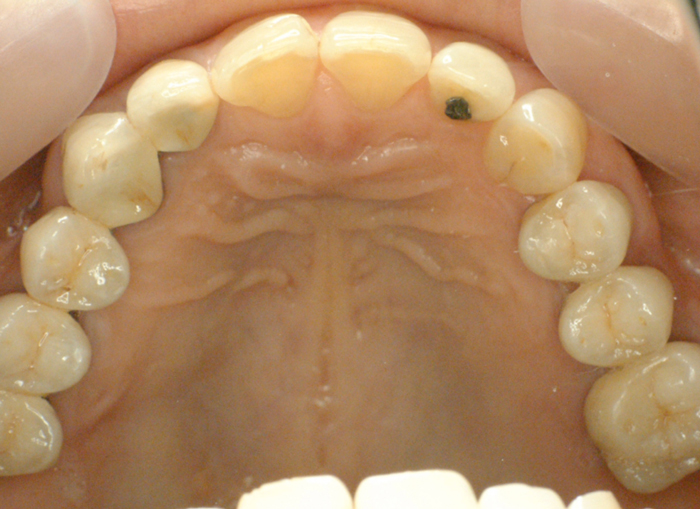

| ●本ケースは、上下顎全歯で患者さんの天然歯が4歯だけ残った症例でした。 結局、上顎にはメタルセラミックスブリッジ補綴を施し、下顎はチャネルショルダーアタッチメントと エクストラコロナル・自家製棒状アタッチメントによるミリング・コンビネーションデンチャーを装備 しています。 ●チャネルショルダーアタッチメントおよび棒状アタッチメントのテクニックに関しては「論文」編 のPDFファイルをご参照くださいませ。 また、製作工程の詳細は「臨床例:補綴用実践的ワックスアップ手順を追う! (コンビ01)」 に良く似た症例を掲載しましたので、ご供覧ください。

| ●下顎右大小臼歯から左犬歯まではメタルセラミックスの連続冠で補綴し、 右大小臼歯、右犬歯および左犬歯、左側切歯の4歯の舌側面にチャネルショルダー内冠 と棒状アタッチメントをミリング加工した。 チャネルショルダー外冠および棒状アタッチメントはパラレルミリング加工しているので、 精密な摩擦抵抗力を持った適合精度が求められます。 内冠の長径および幅径によっても、鋳造システムによる埋没工程の混液比や混水比が 変わってきますので、「コンビネーション用のチェックリスト」を制作し、データを分析しよう。